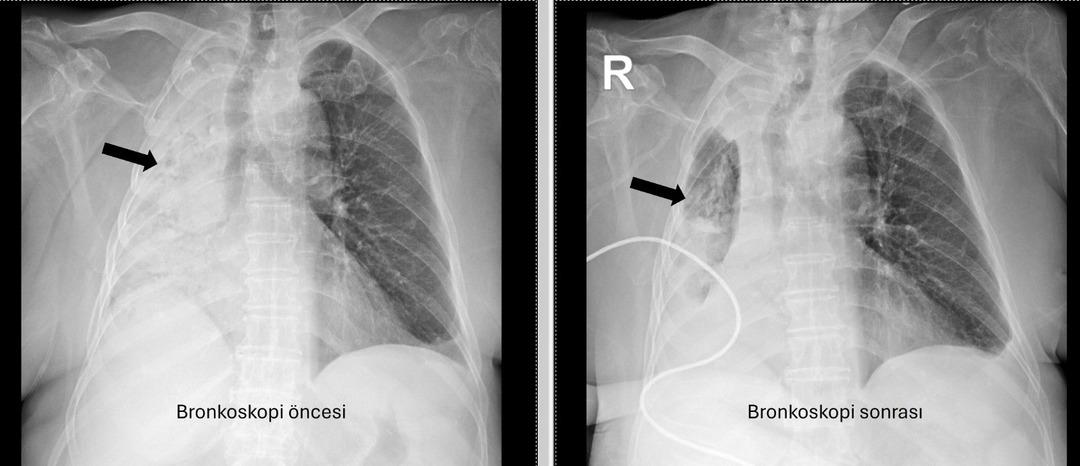

Pau Ökr Hastaneleri Göğüs Hastalıkları Bölümü. Prof.dr. Üye Dr.Köksel Altōiş Ergur, sağ akciğerler tarafından yapılan sınavlar için tamamen kapatıldı. Acil bronkoskopi planlandı ve prosedür derhal gerçekleştirildi. Dr. Altenishık ergur, hava yollarını incelerken çok yoğun ve karanlık bir salgılama ile esnek bir “bronkoskop” (esnek, katlanabilir), ancak hava yollarının derinlemesine temizlenmesini takiben, bir olaydan dolayı dönüştürüldüğünü ve berrak olduğunu, bir olaydan dolayı dönüştürüldüğünü açıkladığını açıkladığını açıkladığı açıktır. Vücudun açık olduğu açık olduğu açık olduğu açık olduğu açıktı. genel anestezi ile yapılmıştır;

Prof. Alküzek Ergur, hastanın trakeasının nasıl engellendiğini açıkladı: “Havayollarında sıvı emen aspiratörün gücünü kullanarak nesneyi çıkarmak mümkün oldu. Hastanın hastanın tekrar yediği pizzada yediği pizza için daha önemli olduğu öğrenildi.